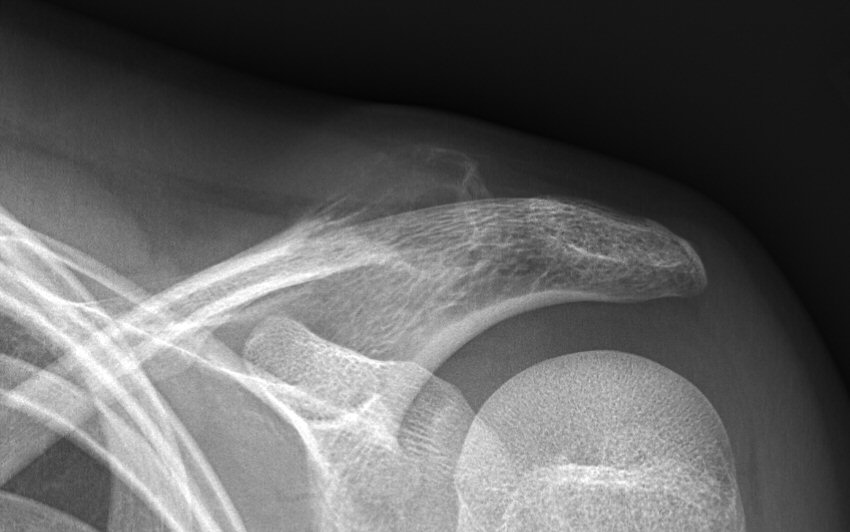

Enkel bencysta med fraktur, andra bilden efter 8 månader, på väg mot utläkning